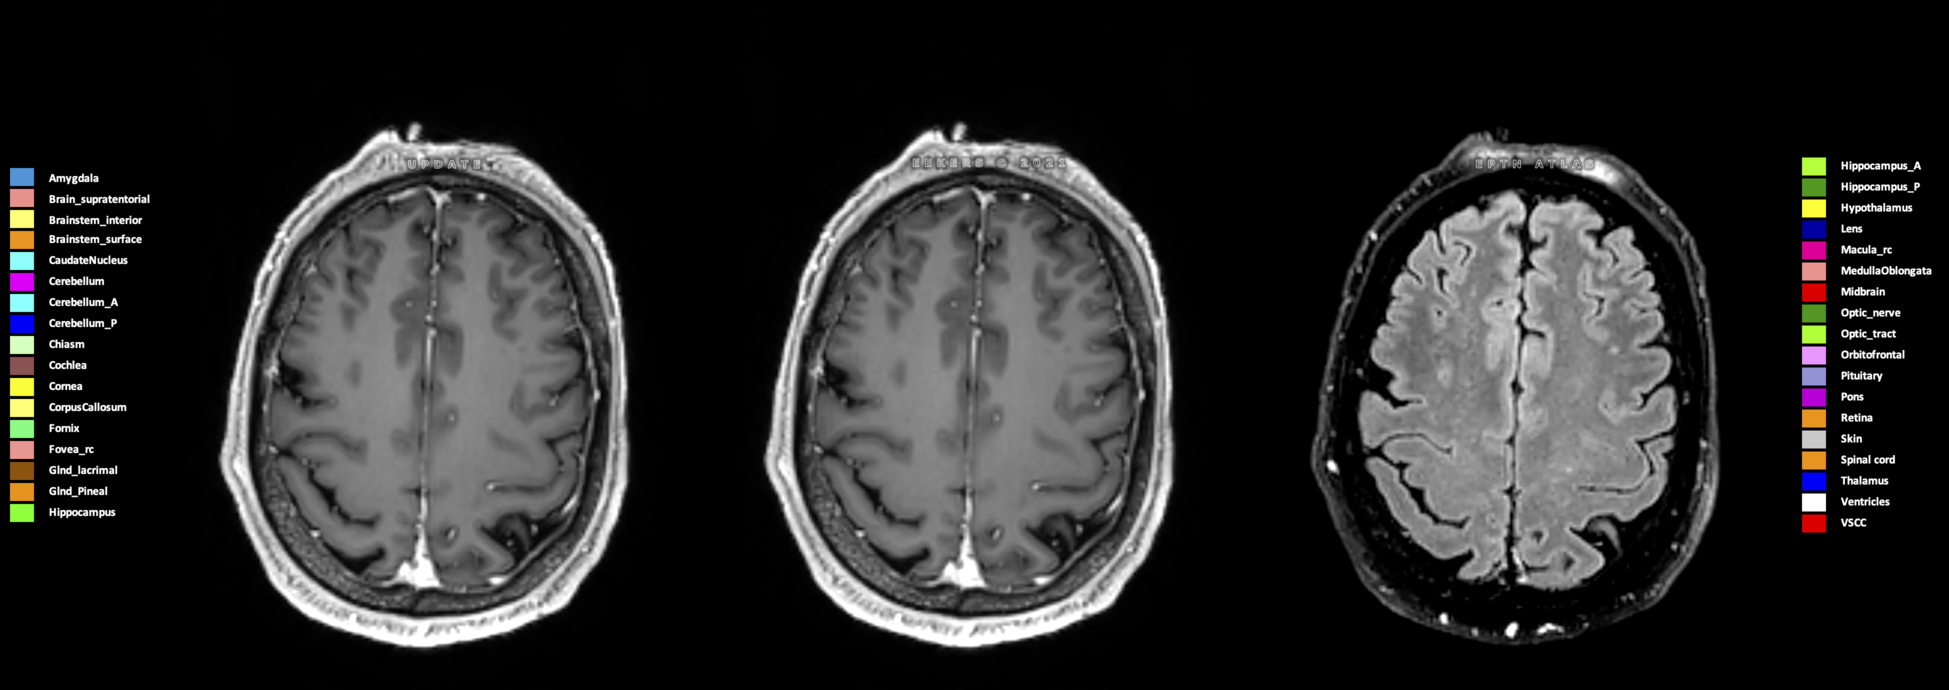

Three-dimensional delineation of the 25 consensus OARs for neuro-oncology are shown on CT (WW/WL 120/40, 3000/600), 3T MR images, (T1Gd, T2FLAIR 1mm) and 7T MR (MP2RAGE 0.7 mm). All are presented in transversal, sagittal and coronal view.